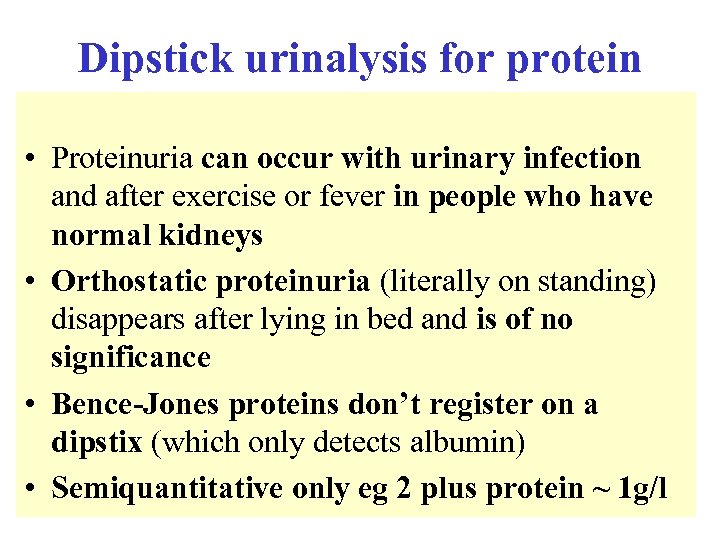

Dipstick urinalysis for protein • Proteinuria can occur with urinary infection and after exercise or fever in people who have normal kidneys • Orthostatic proteinuria (literally on standing) disappears after lying in bed and is of no significance • Bence-Jones proteins don’t register on a dipstix (which only detects albumin) • Semiquantitative only eg 2 plus protein ~ 1 g/l

Dipstick urinalysis for protein • Proteinuria can occur with urinary infection and after exercise or fever in people who have normal kidneys • Orthostatic proteinuria (literally on standing) disappears after lying in bed and is of no significance • Bence-Jones proteins don’t register on a dipstix (which only detects albumin) • Semiquantitative only eg 2 plus protein ~ 1 g/l